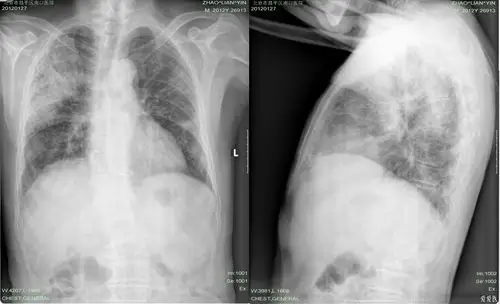

【讨论】左肺蜂窝状改变84289【随访反馈】

【病例讨论】蜂窝肺专题,我也发一例 [病例帖]

【病例讨论】蜂窝肺改变-迁延3个月,抗生素应用仍不见好转